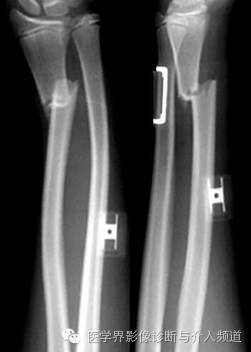

14、Galeazzi 骨折

桡骨中段骨折并下桡尺关节脱位。摔倒时用手撑地或直接暴力打击腕关节背侧造成。